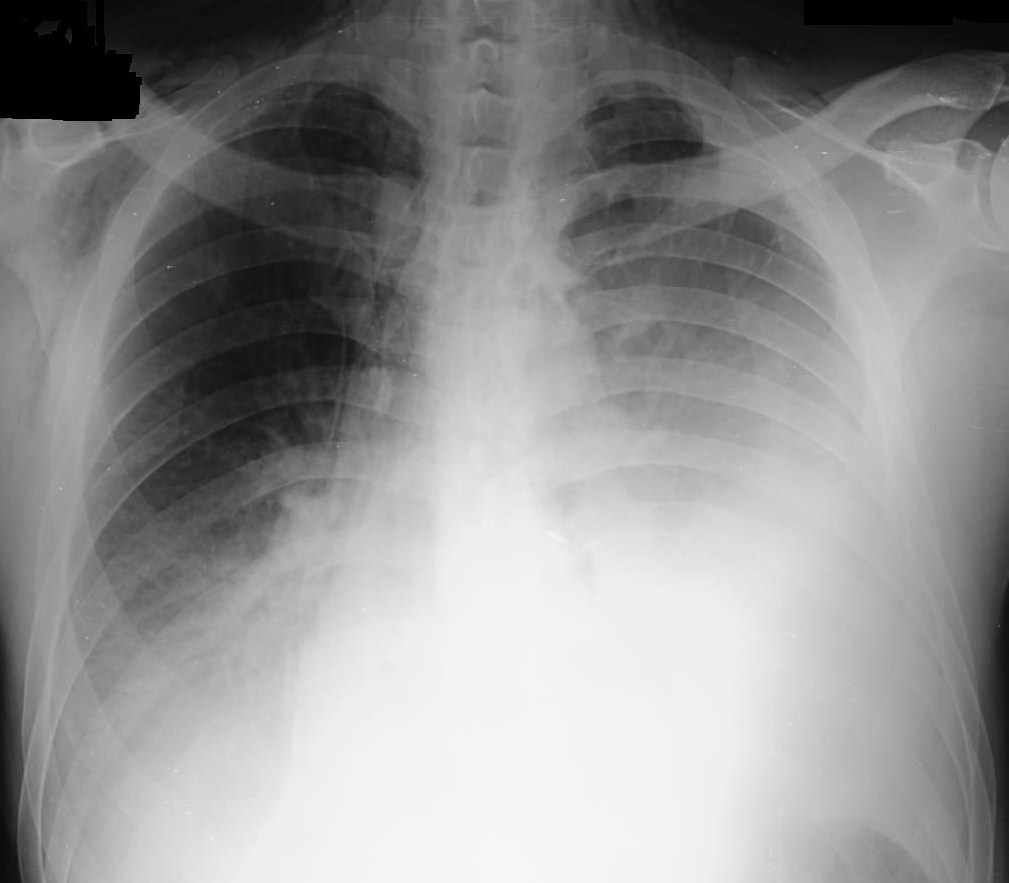

Peripheral WBC count = 14,000/cubic millimeter, and  the chest x-ray (fig. 1) showing bilateral air space disease, left pleural effusion, pneumomediastinum and subcutaneous emphysema. Review of the admission CXR revealed air in the soft tissue of the neck on the right side

Figure 1

Figure 1: Chest X-Ray hospital day 2

What is the main abnormality on this chest radiograph (Figure 3)?

Figure 3

(c) Left sided pleural effusion, subcutaneous emphysema and pneumomediastinum.

Chest x-ray is abnormal in 90% of cases of esophageal perforation but can be normal if taken early (3). Pneumomediastinum may be seen as demonstrated above by the radiolucent streaks of free air surrounding the trachea.